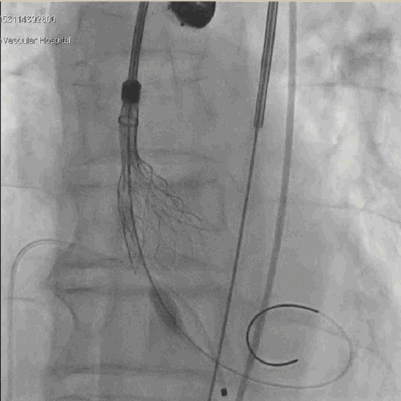

手术过程

主动脉根部造影,冠脉显影良好, 左冠切线位 20mm球囊预扩

“慢-快-慢”步骤释放瓣膜,20mm球囊后扩 瓣膜形态进一步优化

术后评估

球囊后扩后瓣膜形态良好

术前导管测量压差120mmHg;术后导管测量压差8mmHg